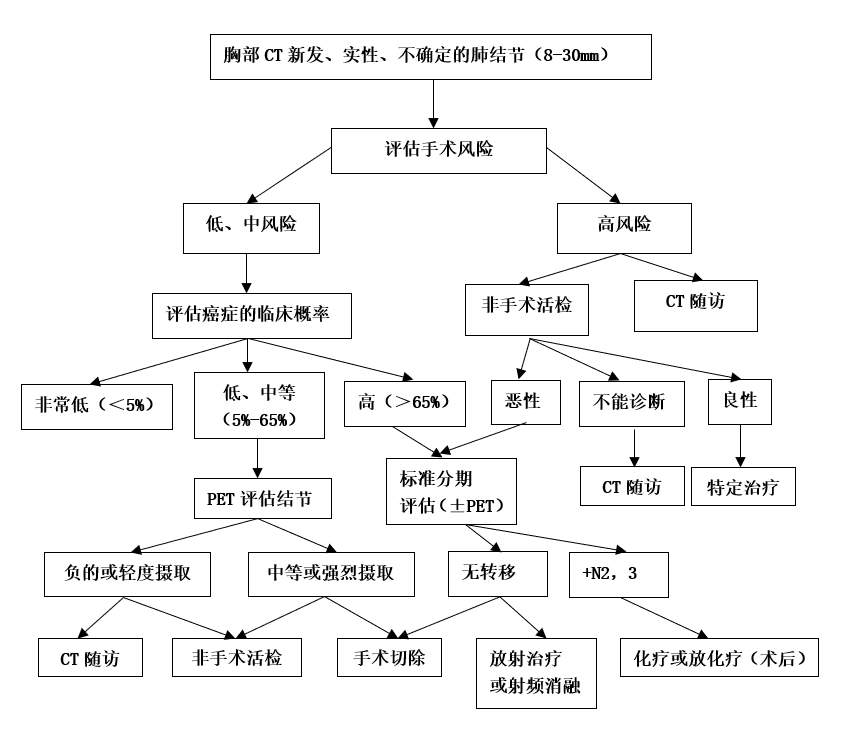

实性肺结节的随访

实性肺结节≥8mm的患者需根据恶性肿瘤危险因素、恶性肿瘤概率(高、中、低)、手术风险、PET-CT代谢等决定是否需要活检或手术切除,具体需要在专科医师专业指导下进行(见图一)。建议该类患者应该尽早到正规医院诊治。如果不能确诊,需进行肺结节多学科会诊(MDT)。

图一:直径8-30mm实性肺结节的临床管理流程